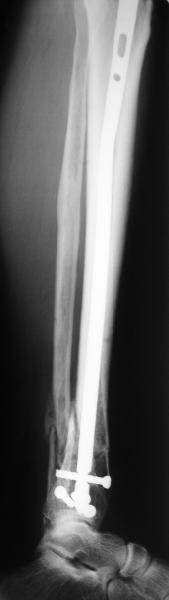

A typical case is attached, also an image with intra-op reduction obtained by a small wire distractor, in the moment of insertion a Poller wire in AP direction. Fixation by a SIGN nail. Despite the fibula was not fixed healing was obtained with the unchanged alignment.

Very interesting application, but is the final position in a little distal varus with some fibula

distraction? Would that have been eliminated by fibula plating?

TDVC> little distal varus with some fibula distraction?

At least both the ankle mortise and tibial alignment look acceptable, don't they?

I am just trying to illustrate that prevention of 1)tibial valgus and 2)loss of reduction can be provided without fibular plating. Small changes of conventional nailing techniques allow to maintain reduction of the tibia reliably without adjunctive fibular stabilization.

In delayed cases acute length restoration performed only in the tibia may leave the fibula shortened thus change the mortise. So it is reasonable to restore length of both bones simultaneously by distractor and fix the fibula not with open reduction and plating but just by a single perQ screw. Example attached.